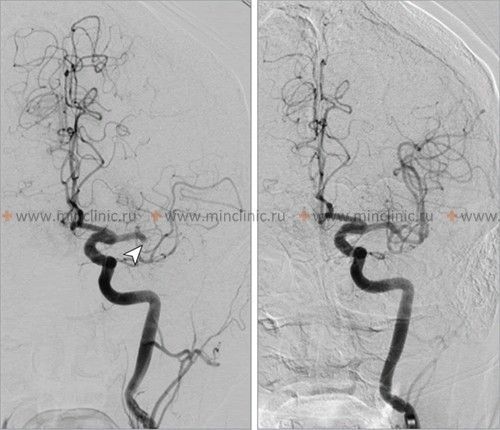

If cerebral artery embolism is suspected, identifying the location of the arterial occlusion and assessing the downstream brain tissue is critical for guiding acute treatment (like thrombectomy) [16, 19]. Non-invasive vascular imaging, such as CT angiography (CTA) or MR angiography (MRA), is typically performed urgently [16]. Conventional catheter-based cerebral angiography (Digital Subtraction Angiography - DSA) provides the highest resolution detail of the vessels but is invasive [14]. It may be performed if endovascular treatment (thrombectomy) is planned or if non-invasive imaging is inconclusive [16, 19]. It's important to note that after several hours or days, an embolus might migrate distally, fragment, or undergo spontaneous lysis (dissolution), meaning that angiography performed later might not show the original occlusion, making the definitive diagnosis of embolic stroke sometimes presumptive based on clinical presentation and infarct pattern [1]. Standard intravenous contrast administration during a routine CT or MRI scan generally lacks the resolution and timing necessary to directly visualize small cerebral emboli within vessels [14].